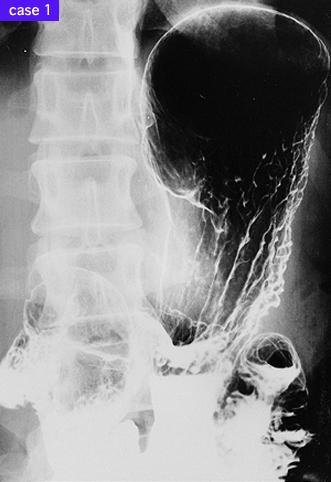

疾患(病理主体)の分類悪性上皮性腫瘍/腺癌

部位(臓器別)胃(部位)/2つ以上

検査方法X-P

腫瘍の肉眼分類4型(びまん浸潤型)/

病変の最大径(ミリ)40以上

腫瘍の深達度s(a)